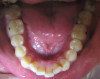

Fig 2. Candidates for hybrid teledentistry include patients with minor (Fig 2), moderate (Fig 3), and advanced crowding (Fig 4).

FIgure 2